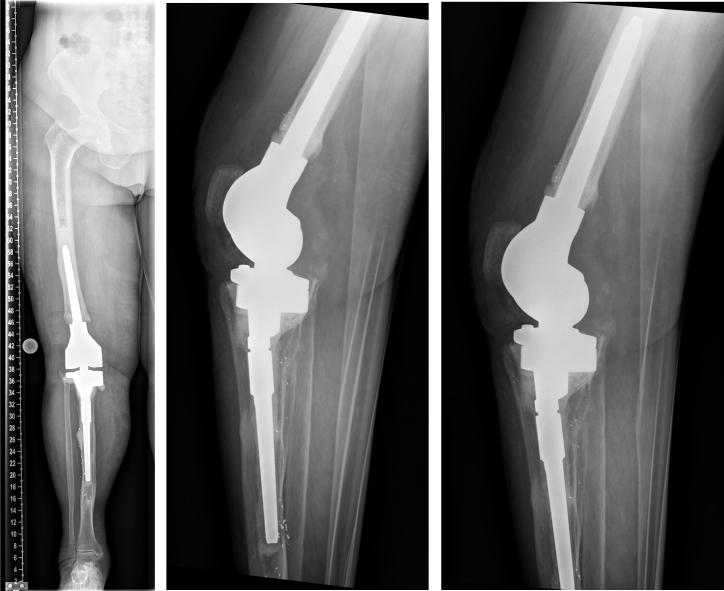

This is a report on a female patient aged 80 years at time of last surgery. The patient was first admitted to our center in 2016. Primary right-sided total knee replacement was carried out in 1994, revision surgery due to aseptic loosening was then performed in 2005. In 2016, aseptic loosening of the components was diagnosed again (Figure 1 [Fig. 1]). Revision surgery was carried out with distal femoral replacement (Figure 2 [Fig. 2]). In 2020, the patient presented to us with insufficiency of the extensor apparatus. According to the clinical picture, especially the macroscopic findings during surgery, infection could not be ruled out. Therefore, explantation of the components was carried out with implantation of a cement spacer. The histological and microbiological findings ruled out infection. Therefore, an intramedullary arthrodesis of the knee was carried out during the same hospital stay (Figure 3 [Fig. 3]). In 2022, the patient again complained of pain and we detected loosening of the femoral component. Despite the fact that no microbes were ever isolated in the right knee, we suspected low grade infection, as loosening occurred within less than 2 years accompanied by local signs of infection (Figure 4 [Fig. 4]). Explantation was carried out with implantation of a cement spacer with intramedullary carbon nails (Figure 5 [Fig. 5]). Yet, the histological and microbiological investigations ruled out infection.

Figure 3: In 2020. Left: Explantation of the components was carried out with implantation of a cement spacer. Right: Intramedullary arthrodesis of the knee

Figure 4: In 2022, local signs of infection